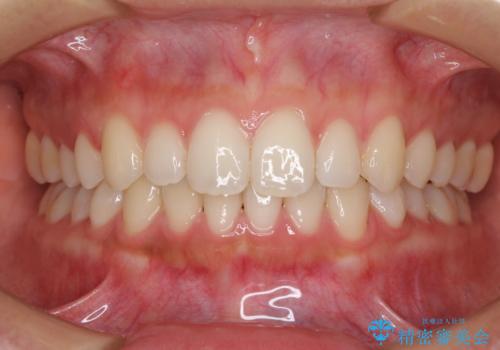

前歯のデコボコをインビザライン矯正で綺麗に改善

気になる段差を納得いくまで改善させたため、治療期間は長くなりましたが、綺麗な仕上がりとなりました。